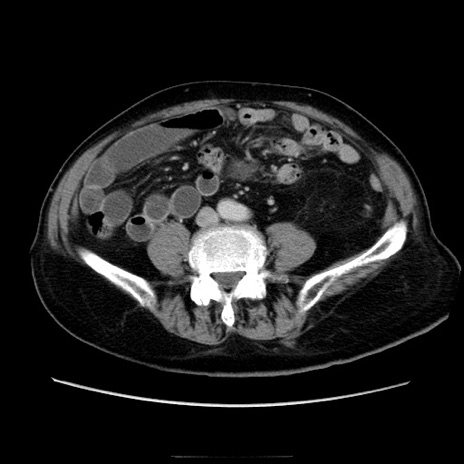

症例21(横断像)

【症例】70歳代男性

【主訴】腹痛

【現病歴】肝硬変・肝細胞癌にてかかりつけの方。約9時間前に食後より腹痛出現。症状が徐々に増悪し、嘔吐出現したため来院。

【既往歴】肝硬変、肝細胞癌(RFA、TACE後)

【身体所見】意識清明、表情苦悶様、BT 36℃、BP 129/78mmHg、P 88bpm、SpO2 97%(RA)、右上腹部から心窩部にかけて圧痛あり、反跳痛なし、筋性防御あり。

【データ】WBC 5800、CRP 0.16